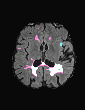

In recent years, data-driven machine learning (ML) methods have revolutionized the computer vision community by providing novel efficient solutions to many unsolved (medical) image analysis problems. However, due to the increasing privacy concerns and data fragmentation on many different sites, existing medical data are not fully utilized, thus limiting the potential of ML. Federated learning (FL) enables multiple parties to collaboratively train a ML model without exchanging local data. However, data heterogeneity (non-IID) among the distributed clients is yet a challenge. To this end, we propose a novel federated method, denoted Federated Disentanglement (FedDis), to disentangle the parameter space into shape and appearance, and only share the shape parameter with the clients. FedDis is based on the assumption that the anatomical structure in brain MRI images is similar across multiple institutions, and sharing the shape knowledge would be beneficial in anomaly detection. In this paper, we leverage healthy brain scans of 623 subjects from multiple sites with real data (OASIS, ADNI) in a privacy-preserving fashion to learn a model of normal anatomy, that allows to segment abnormal structures. We demonstrate a superior performance of FedDis on real pathological databases containing 109 subjects; two publicly available MS Lesions (MSLUB, MSISBI), and an in-house database with MS and Glioblastoma (MSI and GBI). FedDis achieved an average dice performance of 0.38, outperforming the state-of-the-art (SOTA) auto-encoder by 42% and the SOTA federated method by 11%. Further, we illustrate that FedDis learns a shape embedding that is orthogonal to the appearance and consistent under different intensity augmentations.